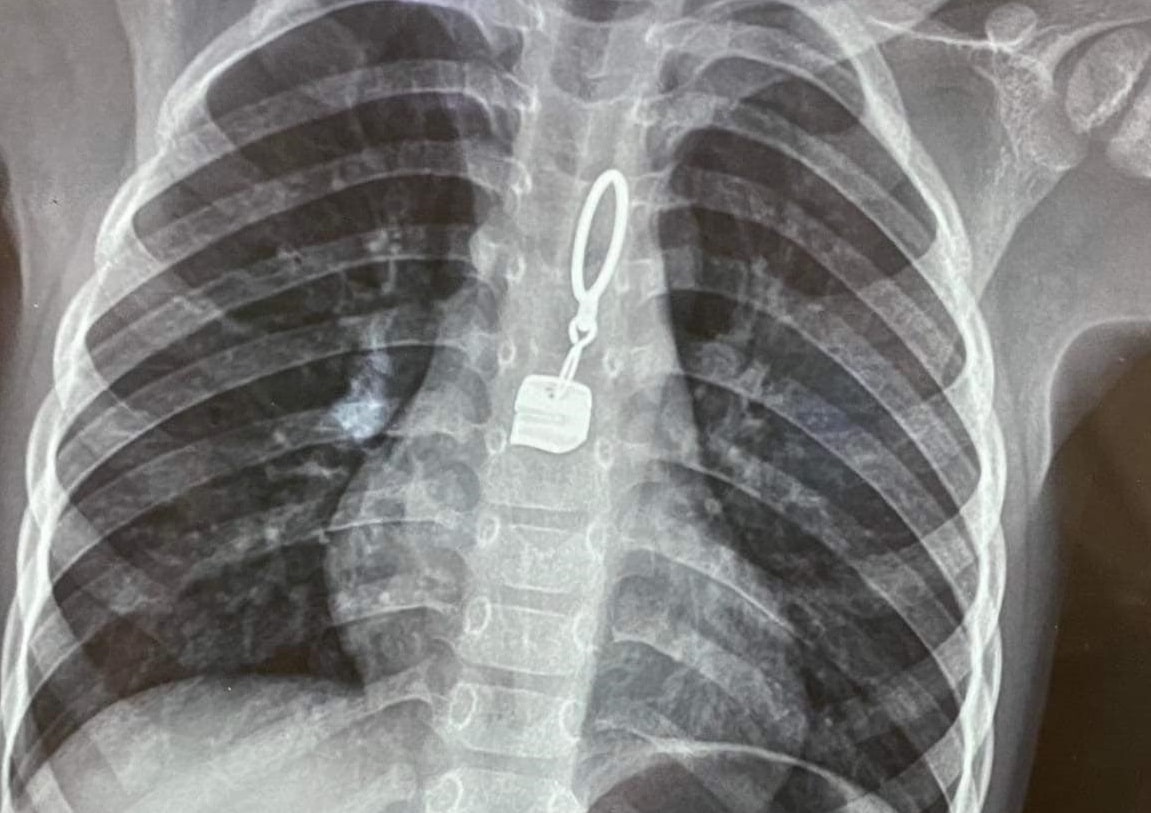

Ngày 5/1, Bệnh viện Đa khoa tỉnh Hà Tĩnh cho biết các bác sĩ vừa kịp thời gắp thành công dị vật là một khóa áo kim loại trong thực quản một bệnh nhi bằng phương pháp nội soi.

Chiều tối ngày 4/1, bé V.B.L. (40 tháng tuổi, ngụ xã Kỳ Đồng, huyện Kỳ Anh, tỉnh Hà Tĩnh) quấy khóc nhiều, đau họng. Một lúc sau, mẹ cháu xem lại chiếc áo khoác của bé, phát hiện khóa áo bằng kim loại không còn, nghi ngờ con mình đã nuốt khóa áo. Gia đình vội vã đưa bé đến Trung tâm Y tế huyện Kỳ Anh để thăm khám.

Tại đây, qua chụp chiếu, các bác sĩ phát hiện trong thực quản bé L. có dị vật nên lập tức chuyển bé đến Khoa Nhi – Bệnh viện Đa khoa tỉnh Hà Tĩnh.

Tiếp nhận bệnh nhi, Khoa Nội tổng hợp phối hợp với Khoa Gây mê – Hồi sức tiến hành nội soi thực quản để gấp dị vật ra ngoài cho bệnh nhi. Khoảng 10 phút sau, dị vật được gắp ra khỏi thực quản của bé L., là một khóa áo bằng kim loại rộng khoảng 1cm, dài khoảng 4cm.